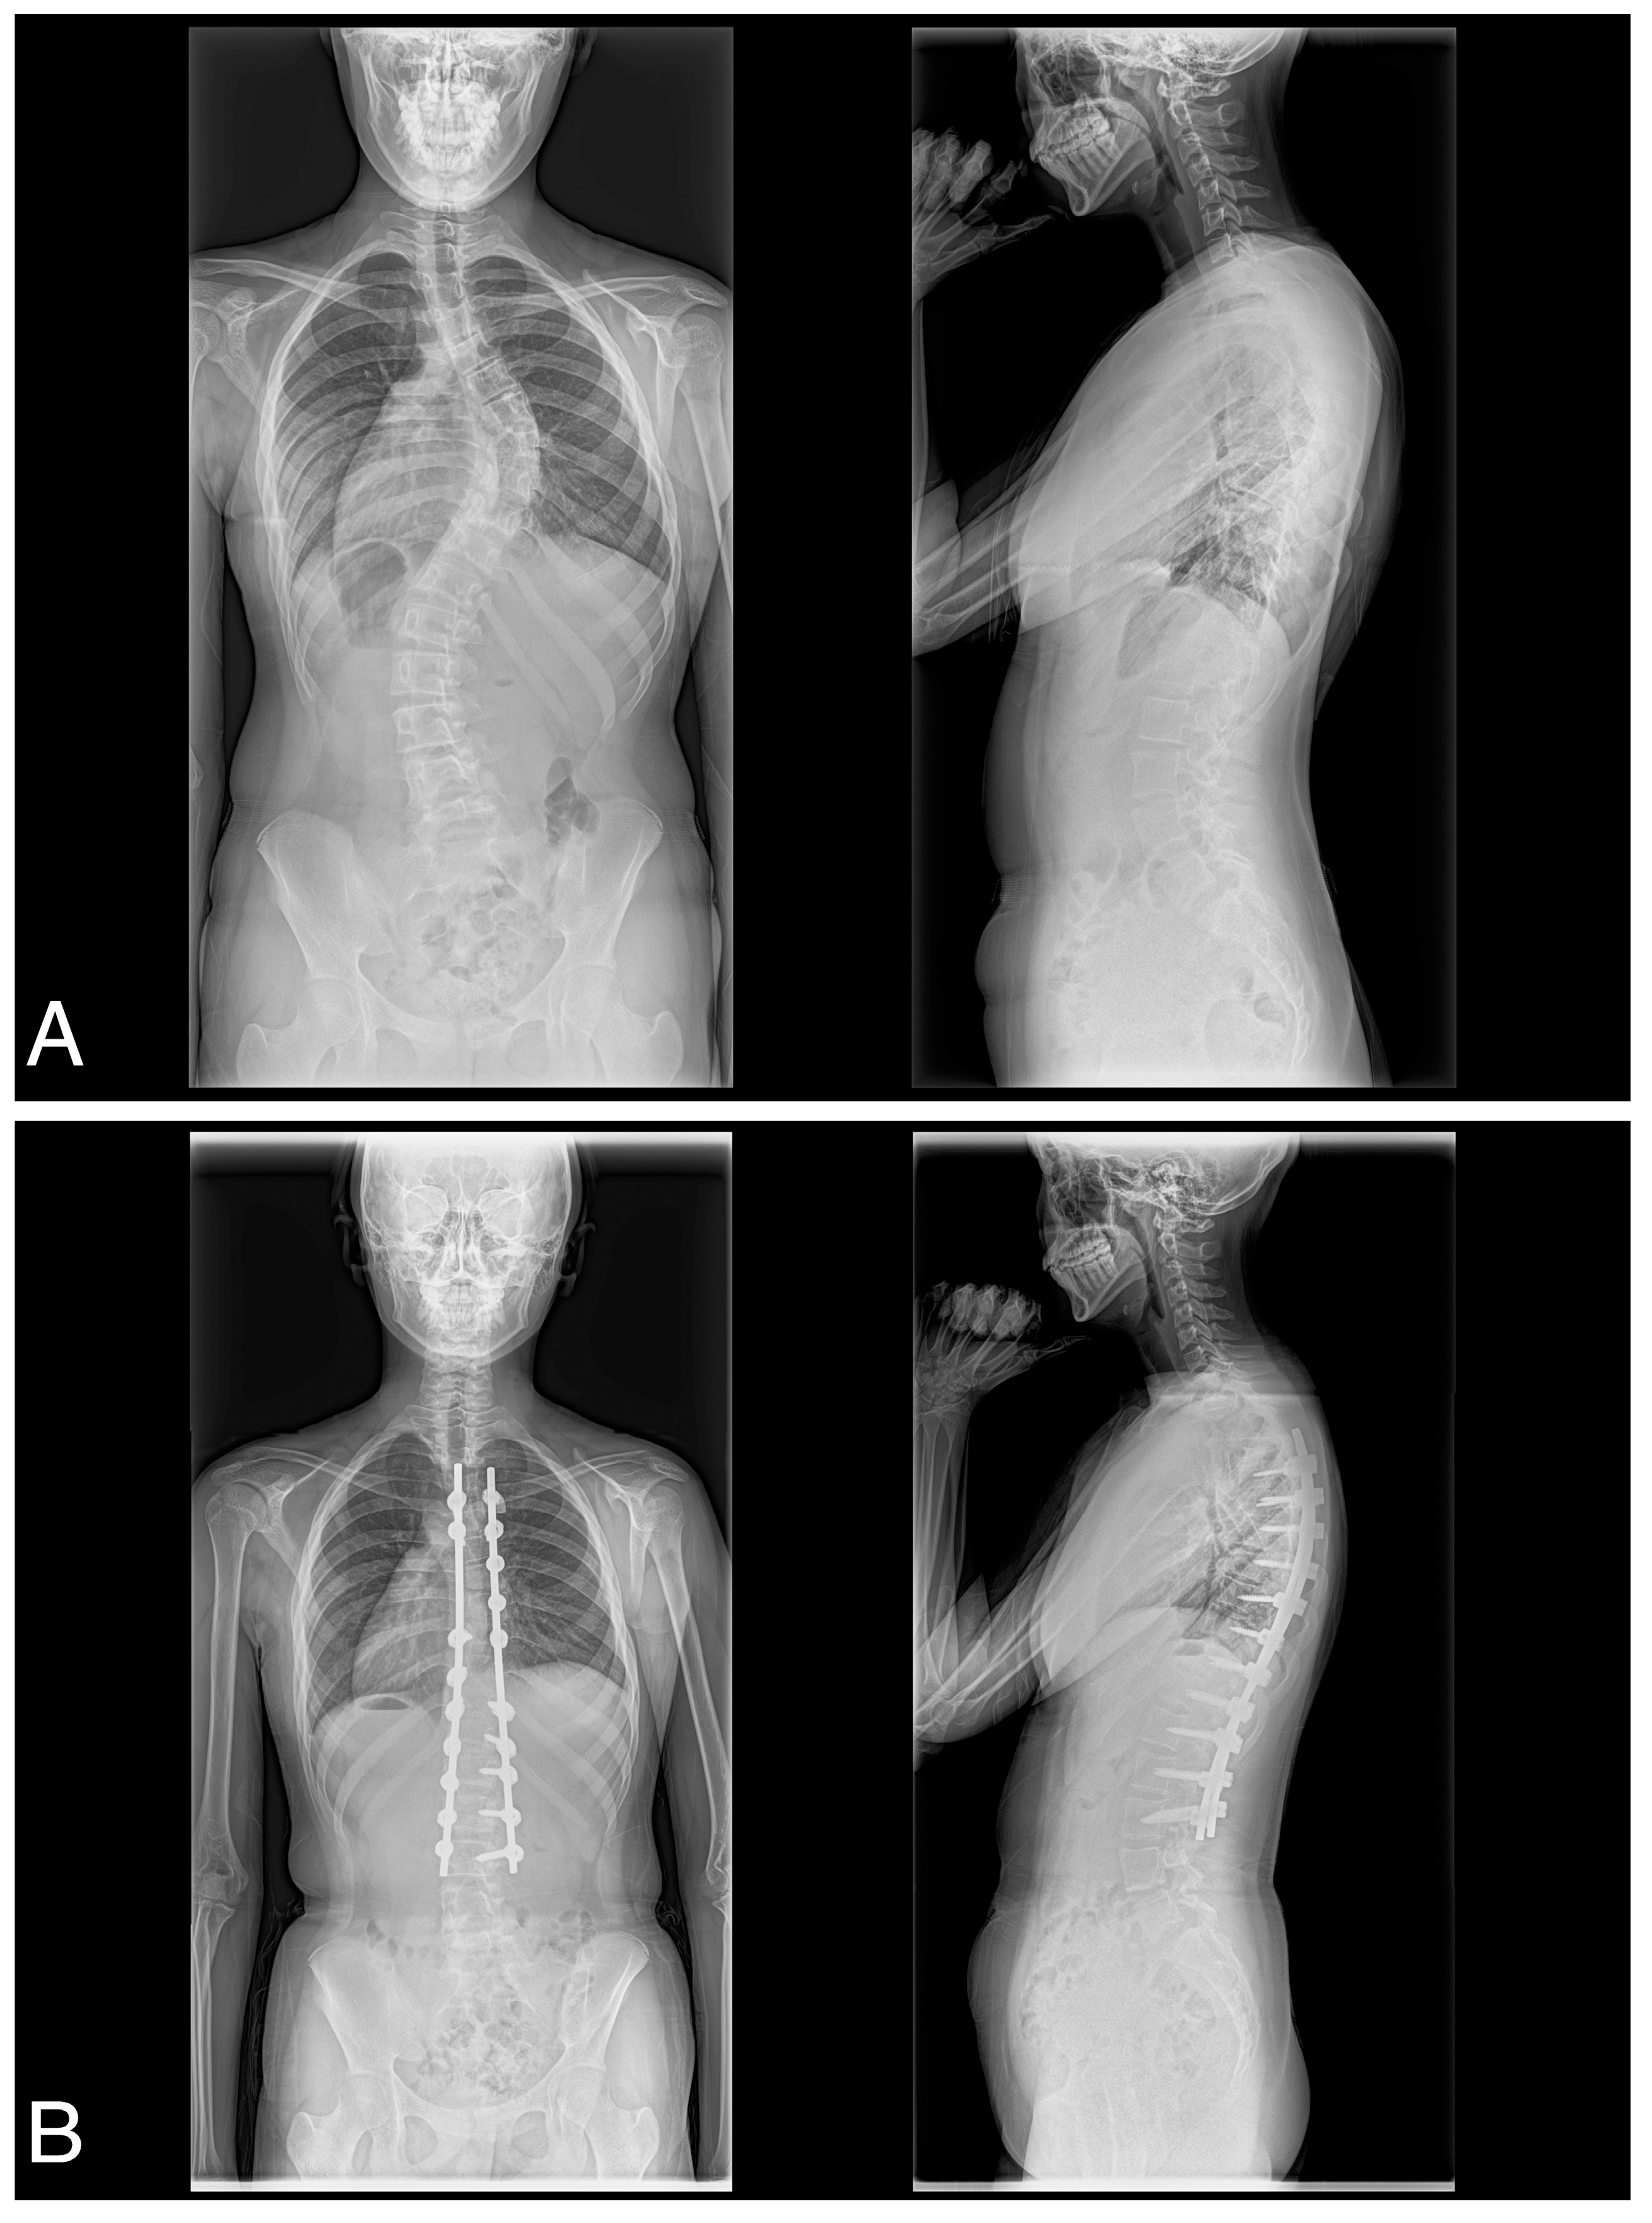

2.2. Surgical Technique